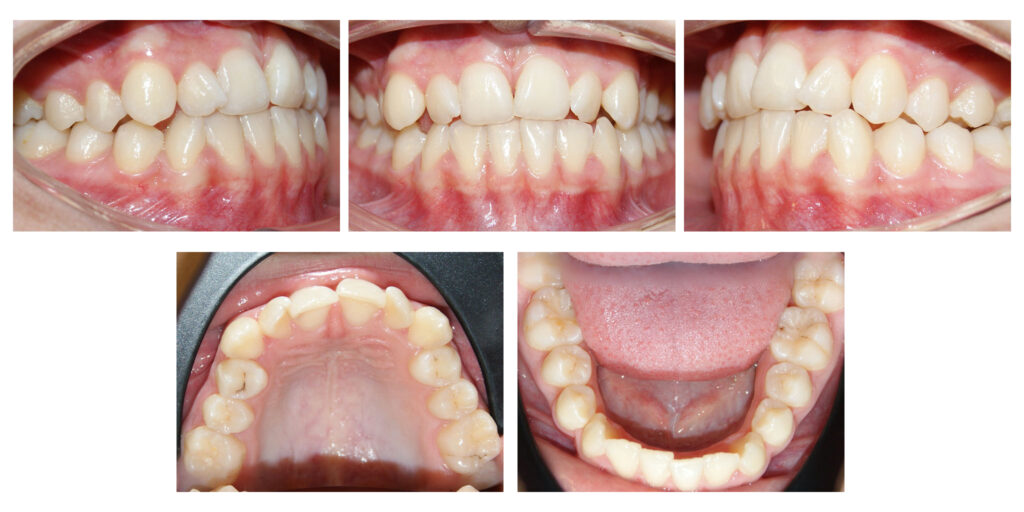

Persistența dinților de lapte peste timpul lor normal de exfoliere determină înghesuirea dinților definitivi. Aparatele dentare fixe sunt instrumentele perfecte pentru alinierea armonioasă a dinților